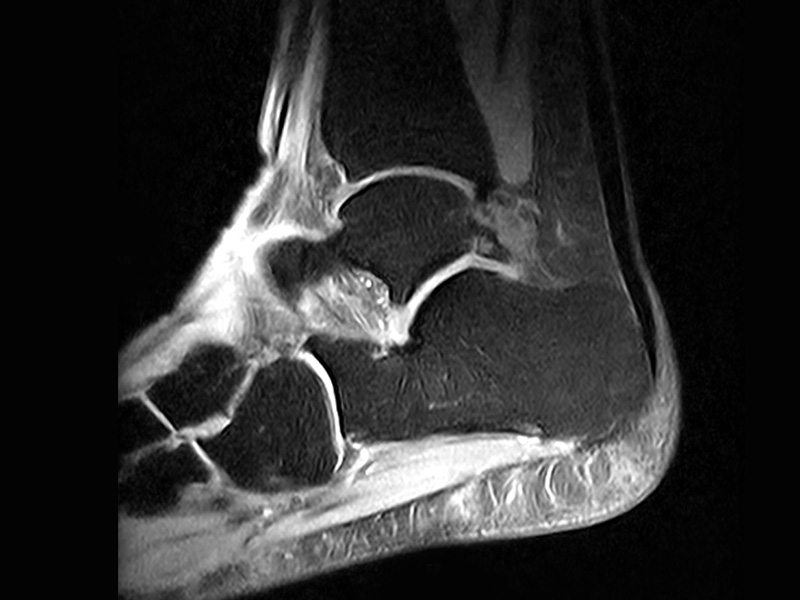

Klinické snímky